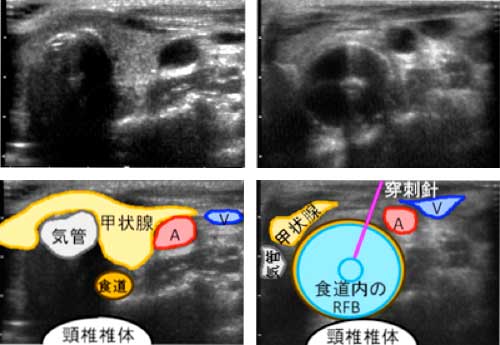

甲状腺の病気があれば、経皮経食道胃管挿入術(PTEG/ピーテグ)は禁忌です。

経皮経食道胃管挿入術(PTEG/ピーテグ)の甲状腺への影響

経皮経食道胃管挿入術(PTEG/ピーテグ)行うにあたり、頸部食道瘻造るための頚部切開で、甲状腺が問題になります。

- 甲状腺が大きかったり、甲状腺腫瘍があったりすると、頚部切開できるスペースが無くなります。

- 甲状腺に頚部切開部の炎症が波及するため、甲状腺機能低下症/橋本病、甲状腺機能亢進症/バセドウ病に何らかの影響を与える可能性があります。